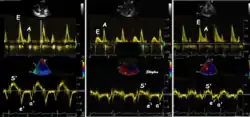

Colour tissue Doppler

Colour tissue Doppler traces from a normal subject Left: traces from the septum and mitral ring. The similarities of the curve shape to spectral Doppler is evident. Right: multiple traces from sites along the septum. The decreasing velocities from base to apex is evident.

Unlike spectral Doppler, colour tissue Doppler samples velocities from all points of the sector, by shooting two pulses successively, and calculating the velocity from the phase shift between them by autocorrelation. The calculation is slightly different from the true Doppler effect, but the result becomes identical. This results in a single velocity value per sample volume. The result is a velocity field of (nearly) simultaneous velocity vectors towards the probe. The advantage of colour Doppler over spectral Doppler is that all velocities can be sampled simultaneously. The disadvantage is that if there is clutter noise (stationary reverberations), the stationary echoes will be integrated in the velocity calculation, resulting in an under estimate. As pulsed wave Doppler are displayed as a spectrum, the colour Doppler values will correspond to the mean of the spectrum (in the absence of clutter), giving slightly lower values. In the HUNT study, the difference in peak systolic values were about 1.5 cm/s.[26]

The local velocities are not the result of the local function, as segments are moved by the action of neighbouring segments. Thus the velocity differences velocity gradient are the main measure of regional contraction, and has become the most important employment of colour tissue Doppler, in the method of strain rate imaging.[27]